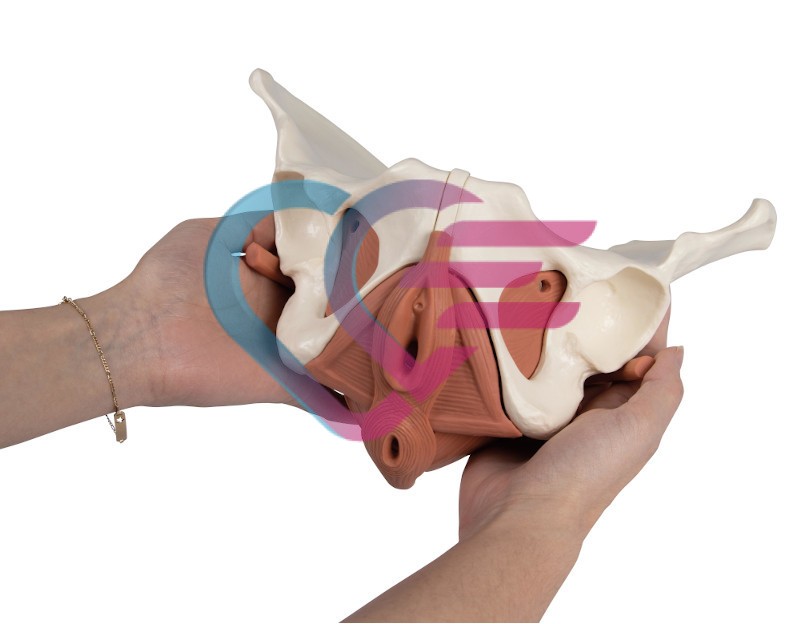

- Poboljšani model dna ženske zdjelice predstavlja zdjelično dno u njegovim slojevima.

- Sastoji se od 12 dijelova.

- Mišići su povezani magnetima što omogućuje njihovo jednostavno uklanjanje radi demonstracije slojeva.

- Prikazani su sljedeći mišići koji se mogu ukloniti:

– musculus obturatorius internus (lijevi i desni)

– musculus piriformis (lijevi i desni)

– musculus coccygeus (lijevi i desni)

– diaphragma pelvis

– urogenitalna dijafragma

– sfinkteri urogenitalnog i digestivnog trakta.